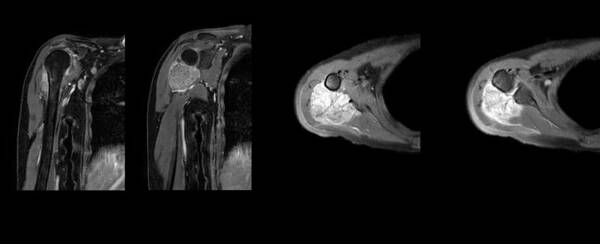

今年56歲的劉阿姨早在數(shù)年前就出現(xiàn)右肩部疼痛,近4月來(lái)明顯加重,夜間酸痛尤甚。當(dāng)?shù)蒯t(yī)院拍片發(fā)現(xiàn)“右肱骨上段皮質(zhì)旁腫瘤病變”,來(lái)到武漢協(xié)和骨科醫(yī)院腫瘤骨科就診。劉建湘教授團(tuán)隊(duì)接診后,進(jìn)行肩關(guān)節(jié)CT和MR檢查發(fā)現(xiàn),腫瘤累及肱骨近端及肩胛骨,范圍廣泛。首先為患者實(shí)行了局部穿刺活檢術(shù),明確病理診斷為“右肩部雙相型滑膜肉瘤”。鑒于該腫瘤為惡性腫瘤,患者目前全身單發(fā)病灶,團(tuán)隊(duì)為患者制訂了個(gè)體化的治療方案——完整切除肱骨上端及一半的肩胛盂,3D打印人工反肩關(guān)節(jié)置換。旨在實(shí)現(xiàn)腫瘤切除與假體重建,從而恢復(fù)患者的正常肩關(guān)節(jié)結(jié)構(gòu)與功能。

經(jīng)過(guò)與患者及家屬溝通病情、治療方案和預(yù)期療效并征得同意后,團(tuán)隊(duì)便開(kāi)始為患者的手術(shù)進(jìn)行緊鑼密鼓的準(zhǔn)備工作。為保證腫瘤完整切除,該手術(shù)需要切除一半的肩胛盂,如何重建的是一個(gè)難點(diǎn)。劉建湘教授、趙磊博士、鐘彬龍博士經(jīng)過(guò)仔細(xì)反復(fù)的閱片、查體及討論,制訂了詳細(xì)手術(shù)計(jì)劃,并與工程師多次商討假體設(shè)計(jì)與加工,在3D打印模型上模擬腫瘤截骨與假體安裝,為患者“私人定制”與其自體骨骼1:1匹配的人工反肩關(guān)節(jié)假體。